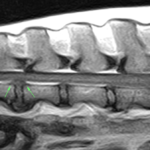

10歳のラブラドールがうまく起立できないとのことで来院されました。神経学的な検査からL7〜S1における腰仙椎間におけるHansen TypeⅡの椎間板ヘルニア、馬尾症候群が疑われました。MRIを撮像したところ、L1~L2にも椎間板ヘルニアが確認されたことから、L7〜S1の椎間板ヘルニアと2ヶ所、同時にPLDDで経皮的に除圧術を行うことになりました。大きな切開を必要としないため翌日退院となります。しばらくは安静にしつつ徐々にリハビリを開始します。